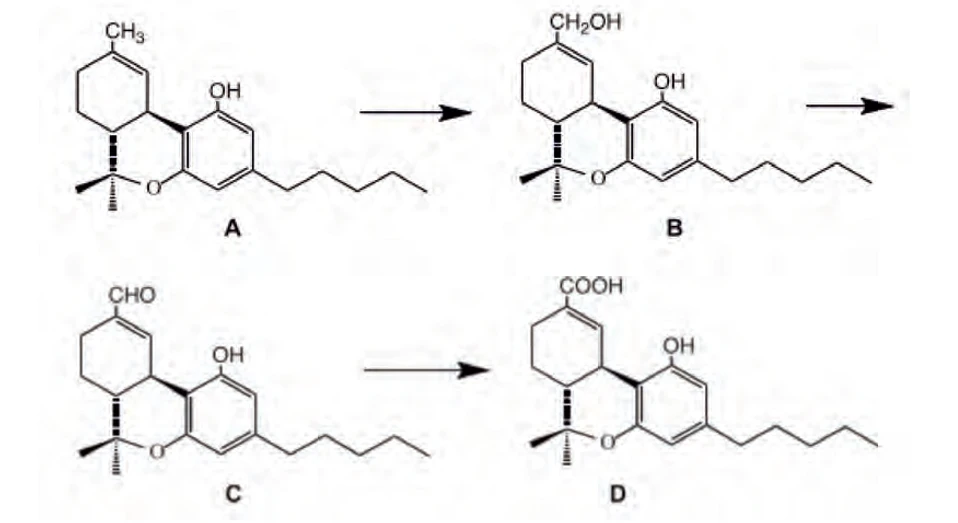

THC se v lidském těle oxiduje cytochromem P452, subtyp 2C9 (CYP2C9) na THC-11-ovou kyselinu (THC-COOH), která nevykazuje psychotropní účinky. Jedná se o tříkrokový proces přes hydroxylovaný a aldehydový intermediát (Obr. 6). THC-COOH a její glukuronidy jsou klíčovými analyty ve vzorcích moči při použití forenzních esejí indikujících užití marihuany (16,26). CBD se metabolizuje podobně. Prvním krokem je hydroxylace na C-7 konci, dochází k vytvoření 7-hydroxy-CBD, následuje další oxidace vedoucí k vytvoření CBD-7-ové kyseliny a hydroxylovaných derivátů této kyseliny. Dále se tvoří glukuronidy těchto oxidovaných metabolitů25.

PČR: Obr. 6 – Schéma metabolismu THC, sloučenina A - Δ9-THC, B – hydroxylový intermediát, C – aldehydový intermediát, D - Δ9-THC-11-ová kyselina (16)

PČR: Obr. 6 – Schéma metabolismu THC, sloučenina A - Δ9-THC, B – hydroxylový intermediát, C – aldehydový intermediát, D - Δ9-THC-11-ová kyselina (16)